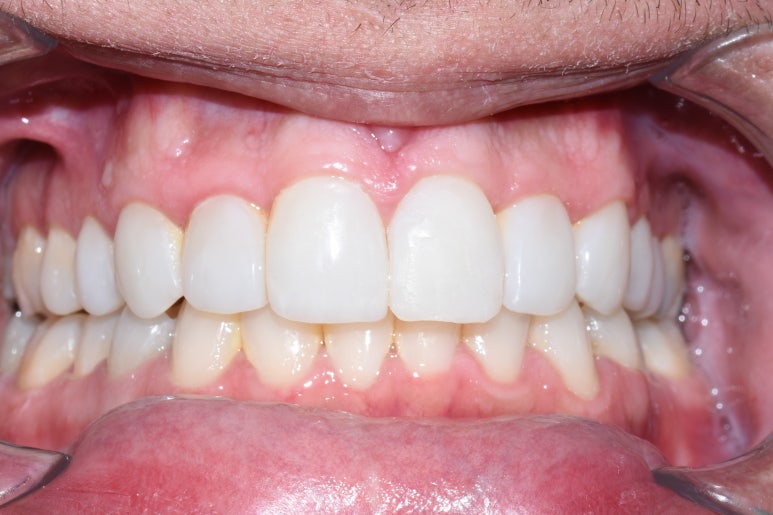

사고 직후 빠진 치아 (왼쪽 사진) -> 윗니 브릿지 및 아랫니 브릿지(오른쪽 사진)

환자분은 넘어졌다고 하셨나? 그랬지만 주변의 증언을 들으면 싸운 것 같다는...

이 환자분은 이미 치아도 빠지고 흔들리는 김에 치아 완전 고르게 해달라고 하셔서

흔들리는 이는 빠지고 치료해야 하는 치아는 처리해서 브릿지를 만들어 드렸고

환자분이 고르고 하얗게 된 이에 굉장히 만족 하셨습니다.